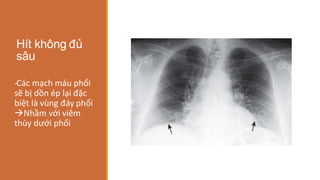

Hít không đủ

sâu

-

‐Các mạch máu phổi

sẽ bị dồn ép lại đặc

biệt là vùng đáy phổi

Nhầm với viêm

thùy dưới phổi